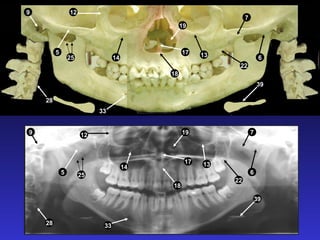

2. Các mốc giải phẫu trên phim toàn cảnh

1. Xoang hàm

2. Hố chân bướm hàm

3. Xương chân bướm

4. Gai bướm

5. Cung xương gò má

6. Lồi khớp xương thái dương

7. Đường khớp gò má thái dương

8. Mỏm gò má

9. Lỗ ống tai ngoài

10. Mỏm chũm

11. Hố sọ giữa

12. Bờ viền ngoài ổ mắt

13. Bờ dưới ổ mắt

14. Lỗ dưới ổ mắt

15. Ống dưới ổ mắt

16. Hốc mũi

17. Vách ngăn mũi

18. Gai mũi trước

19. Xương cuốn dưới

20. Lỗ răng cửa

21. Vòm miệng cứng

22. LồI củ xương hàm trên

23. LồI cầu

24. Mỏm vẹt

25. Khuyết sigma

26. Hố giữa khuyết sigma

27. Mỏm trâm

28. Cột sống cổ

29. Gờ chéo ngoài

30. Ống răng dưới

31. Lỗ ống răng dưới

32. Gai Spix

33. Lỗ cằm

34. Hố tuyến dưới hàm

35. Gờ chéo trong

36. Hố cằm

37. Gờ cằm

38. Gai cằm

39. Xương móng

40. Lưỡi

41. Vòm miệng mềm

42. Lưỡi gà

43. Thành sau họng

44. Dái tai

45. Khoang lưỡi hầu

46. Khoang mũi hầu

47. Khoang vòm miệng lưỡi